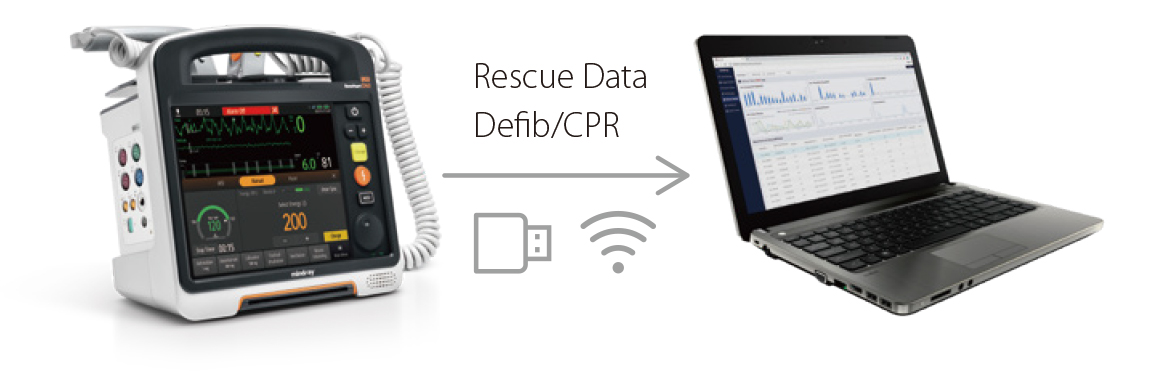

Sesiones de evaluaciÃģn posterior estructuradas

- Los protocolos de sesiones de evaluaciÃģn posterior estructuradas del D60 mejoran el desempe?o de los equipos de reanimaciÃģn en eventos de reanimaciÃģn posteriores.

Hands-on Training

- El modo de formaciÃģn del D60 le ayuda a adquirir experiencia real de funcionamiento.

Los perfiles de configuraciÃģn se pueden personalizar y cargar fÃĄcilmente para diferentes situaciones clÃnicas o requisitos de uso, e incluyen los valores predeterminados, el dise?o de la pantalla y la configuraciÃģn del sistema.